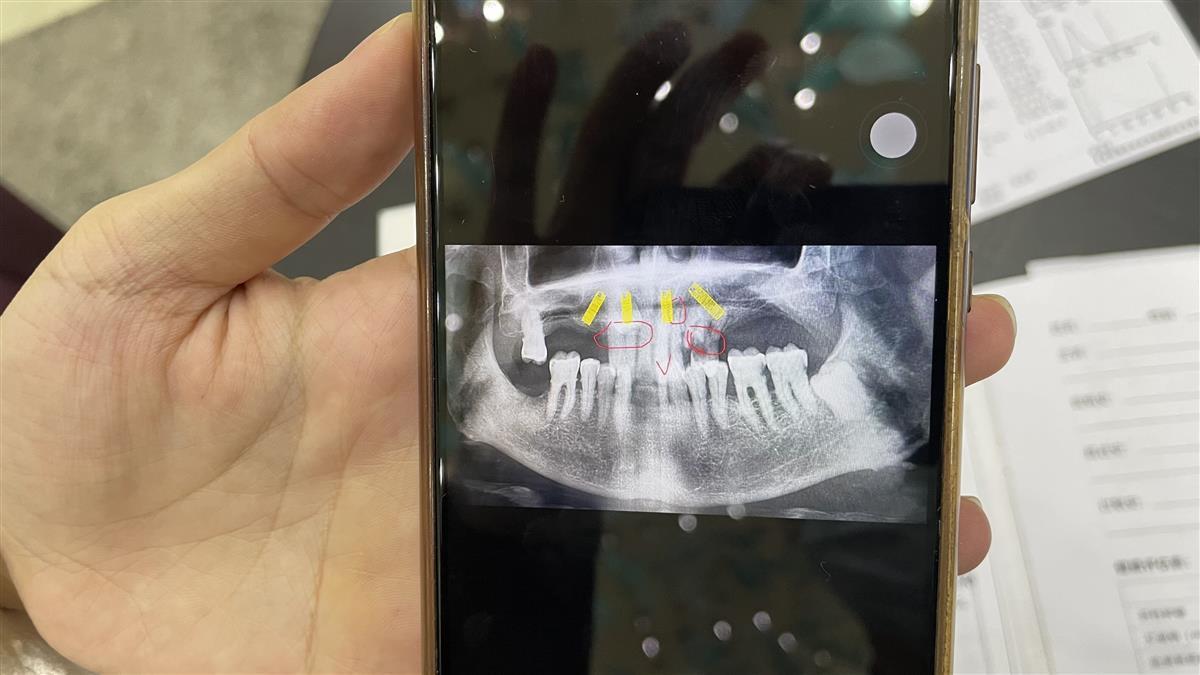

上齒部分前牙區(qū)CT圖

當(dāng)日,極目記者趕到武漢華美整形醫(yī)院,當(dāng)時(shí)接待周爹爹的平女士介紹,經(jīng)CT片和現(xiàn)場(chǎng)檢查綜合診斷,周爹爹的上半口牙的前牙區(qū)的8顆牙,有3顆牙已經(jīng)缺損,有2顆松動(dòng)預(yù)計(jì)一年半載后也會(huì)出現(xiàn)缺損,余下的3顆,2顆牙為埋伏牙(可理解為殘牙、殘冠),1顆好牙,而周爹爹同意的種植牙方案為對(duì)其上齒部分前牙區(qū)種植4顆恢復(fù)上半口14顆牙的半固定修復(fù),這需要對(duì)上半口前牙區(qū)的牙齒全部拔除才能處理,所以醫(yī)生才對(duì)上半口前牙區(qū)的8顆牙全部進(jìn)行了拔除。